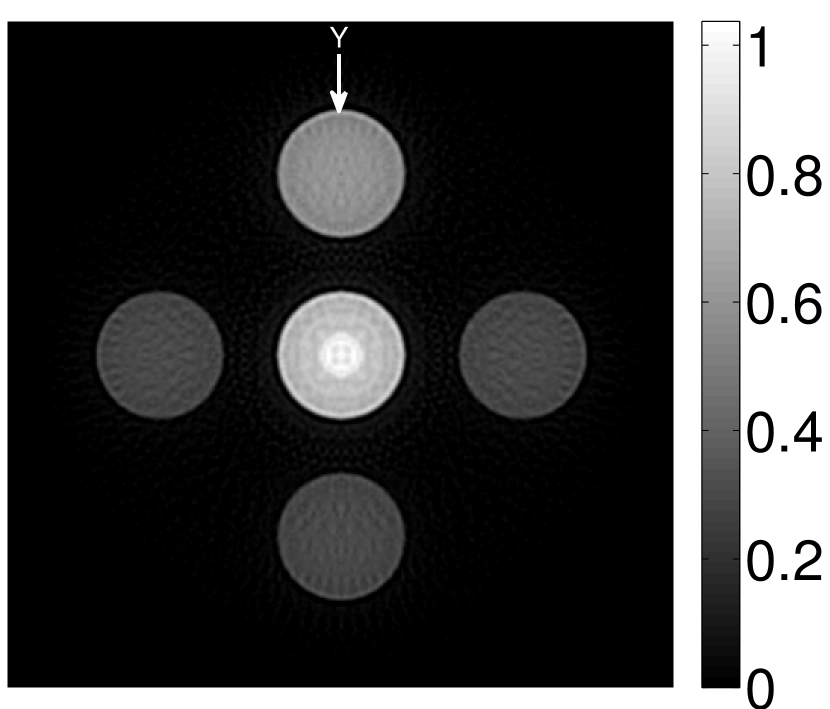

The numerical phantom shown in Figure 1(a) was employed. The phantom had a support area of mm2 and contained six uniform disks that were assigned different values of absorbed optical energy density.

A 2D circular measurement geometry was employed. transducers were evenly distributed on a ring of radius mm that enclosed the phantom. The SOS was assumed to be constant and set at mm/s. Since the simulated data were formed by use of the C-D imaging model in Eqn. (2), no inverse crime was committed. The components of this vector corresponded to equally spaced temporal samples over the interval s. Subsequently, the noiseless voltage vector was obtained by convolving the pressure data with EIR-1 in Figure 1(b).

The reconstruction region ( mm2) was represented by pixels with pixel size mm in each dimension. The initial guess of the EIR employed in the VP algorithm was different than the EIR that was assumed when generating the simulated data. This served to simulate a situation in which an experimentally measured EIR contained errors.

Each element in a real-world transducer array possesses its own EIR. In practice, the differences between the EIRs are sometimes neglected and an EIR corresponding to a single element may be used to represent all elements in the array. In some of the studies below, the EIR employed to initialize the VP algorithm (EIR-2 in Figure 1(b)) and the EIR employed to produce the simulated measurements (EIR-1 in Figure 1(b)) were experimentally measured from two different transducer elements in a circular transducer array (see Sec. VI-B). EIR-1 was measured by temporally integrating the PA signal produced by a point source positioned at the focus of the transducer. EIR-2 was measured by use of the method reported in [RNR2011]. In order to investigate the sensitivity of the VP algorithm to the initialization of the EIR, we employed different EIRs obtained by degrading EIR-1 as described later. When solving the sub-problem in Line-2 of Algorithm 1, was initialized as the zero vector. Algorithm 1 was terminated after 500 iterations, since it was observed that the changes in the reconstructed images with more iterations were negligible. When implemented by use of a single core of an Intel Xeon E5-2640 CPU, each iteration required approximately 7s to complete.

Figure 2(a) shows the image reconstructed by use of the conventional iterative method that utilized a system matrix based on EIR-2. Different values of the regularization parameter from the interval were considered. The reconstructed image with the value of that minimized the RMSE was chosen to represent the best performance of the conventional iterative method. Figure 2(a) and the profile in Figure 2(c) demonstrate that the use of an inaccurate EIR can result in strong artifacts and distortions in images reconstructed by use of the conventional methods.

When the VP algorithm was applied, different values of the regularization parameter from the interval and from the interval were considered. The image that minimized the RMSE was chosen and displayed in Figure 2(b). As revealed by this image and the profiles in 2(c), the VP algorithm yielded an image with fewer artifacts and distortions, and image fidelity was improved as reflected by the reduced RMSE.

V-A3 Effect of data incompleteness

Incomplete, or sparsely sampled, data sets are sometimes acquired in practice. To study the effect of data incompleteness on the VP algorithm, we reconstructed images from data corresponding to half of the equally spaced transducers (). Because the data were noiseless, no explicit regularization was employed () in the conventional reconstruction algorithm. However, the explicit regularization was still employed in the VP algorithm because of the ill-posed nature of the joint reconstruction problem. The results are shown in Figure 5. As expected, use of the incomplete data set resulted in less accurate reconstructed images for both the conventional iterative reconstruction method and the VP algorithm. However, this effect was more pronounced for the VP algorithm. Note that for the VP algorithm, larger values of the regularization parameters were applied when the incomplete data set was employed than when the complete data set was employed (Figure 5(h) and 5(g)).